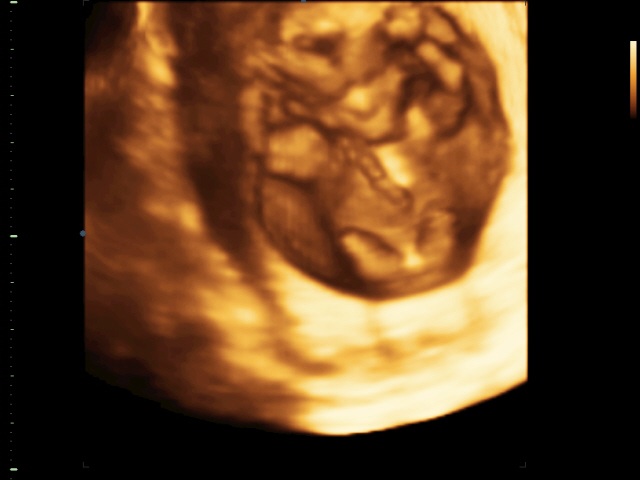

Вопросы про УЗИ, обследования и анализы: что, где, как, когда? Мы сходили вчера на 3д. Он был очень активный, бегал, танцевал нам, физкультурой занимался! Теперь в голове не укладывается, как я НЕ чувствую такую движуху внутри себя?!?!?!

Врач сказала - по отсутствию половой щели, я могу судить, что может это будет мальчик.

Но лично я сто раз видела писюн!!! Мне с какого ракурса не покажи, одни яйца)))) и Влад тоже сказал что мальчик. Как только включили экран, он лежал точно как я на кушетке. Рука за головой, вторая на груди))))) Похож на меня, только нос Воронинский)))) на фото не видно, но во время сеанса несколько раз - копия Я!

Теперь вопрос/тема для обсуждения, на сколько можно серьезно относится к показаниям "отсутствие половой щели" ???? Мне казалось на этом сроке никаких щелей, у обоих бугорки, просто слегка разные.....